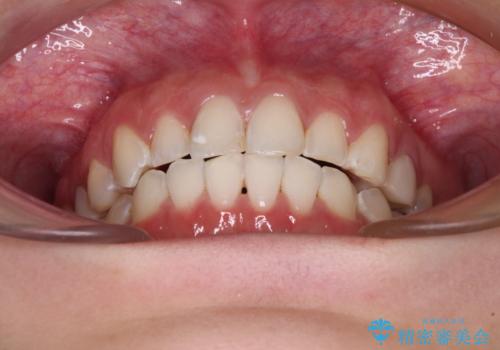

- 前歯の歯列不正を気にして来院された患者様です。

インビザラインでの矯正治療を希望されていましたが、奥歯の咬み合わせがインビザライン単独では改善困難と判断されたので、補助装置を併用することとしました。

まずは裏側の装置やワイヤー矯正を用いて歯列幅の狭い上顎を側方に拡大しつつ全体を後方に移動させ、その後インビザラインにて歯列を整えることとしました。